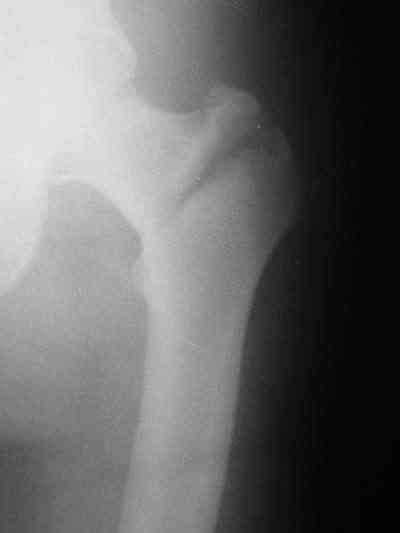

Около 10 дней назад выполнил остеосинтез бедренной кости LC-DCP и DHS по поводу фрагментарного оскольчатого перелома в средней трети и чрезвертельного перелома.

Снимки в приложении.

В приложении и имеющийся в наличии брейс. Приношу извинения за низкое качество снимков.

Качество снимков приемлемое. С нагрузкой категорически не надо спешить - только при уверенных рентгенологических признаках сращения на обоих уровнях в данном случае. Т.е. не только на диафизе, но и в вертельной области. При безупречном синтезе DHS ранняя нагрузка в этой зоне была бы безопасна, все определялось бы сращением диафиза. А поскольку винт в DHS сделали ну о-очень короткий, то ойкнуть не успеете, как

проксимальный отдел бедра в варус кувыркнется.

Глубокоуважаемый Никита!На бедре стоило бы обязательно провести межфрагментарный стягивающий винт и предварительно надо бы слегка изогнуть пластину,ну и может быть трансплантат по внутренней поверхности.А параллельно большому винту DHS провести спонгиозный винт для ротационной стабильности.Так,что с нагрузкой не нада тараписся!

Алексей Семенистый 28 Июль 2006, 20:08

Уважаемый Никита, очень меня расстроило не качество снимков, а сам остеосинтез. Вертельный перелом, пожалуй, еще срастется. А диафиз может преподнести ожидаемое, предуготованное осложнение: несращение и перелом импланта, даже если это суперфмрменная пластина.:(